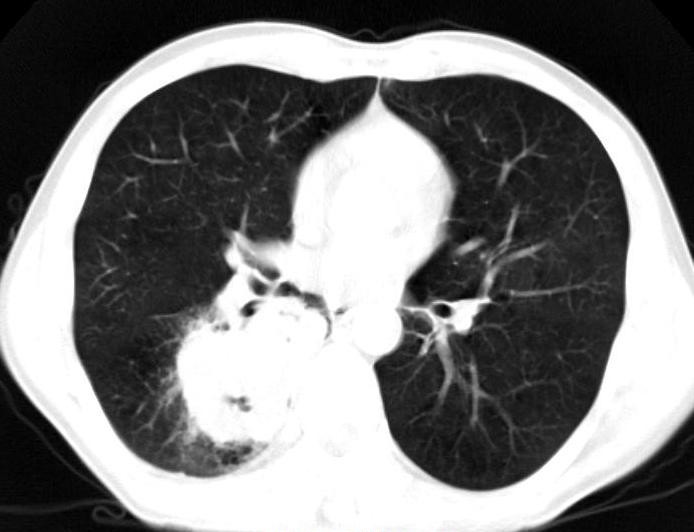

肺是胸部最主要的器官之一,肺部无论是筛查也好,诊断也好,一个CT基本上就可以解决。并且,现在无论是肺结节还是肺肿瘤筛查,胸部CT已经成为了常规。

如果有条件,体检每年能加上胸部CT最好(齐大夫所在医院每年体检都要做胸部CT,非常有必要。而每年我们也会发现几个早期肺癌的同事和患者)。关于辐射问题,一次CT的辐射剂量远远达不到致病程度,大家不要再顾及辐射问题(笔者自己每年都会做一个胸部CT体检,你们还怕啥)。